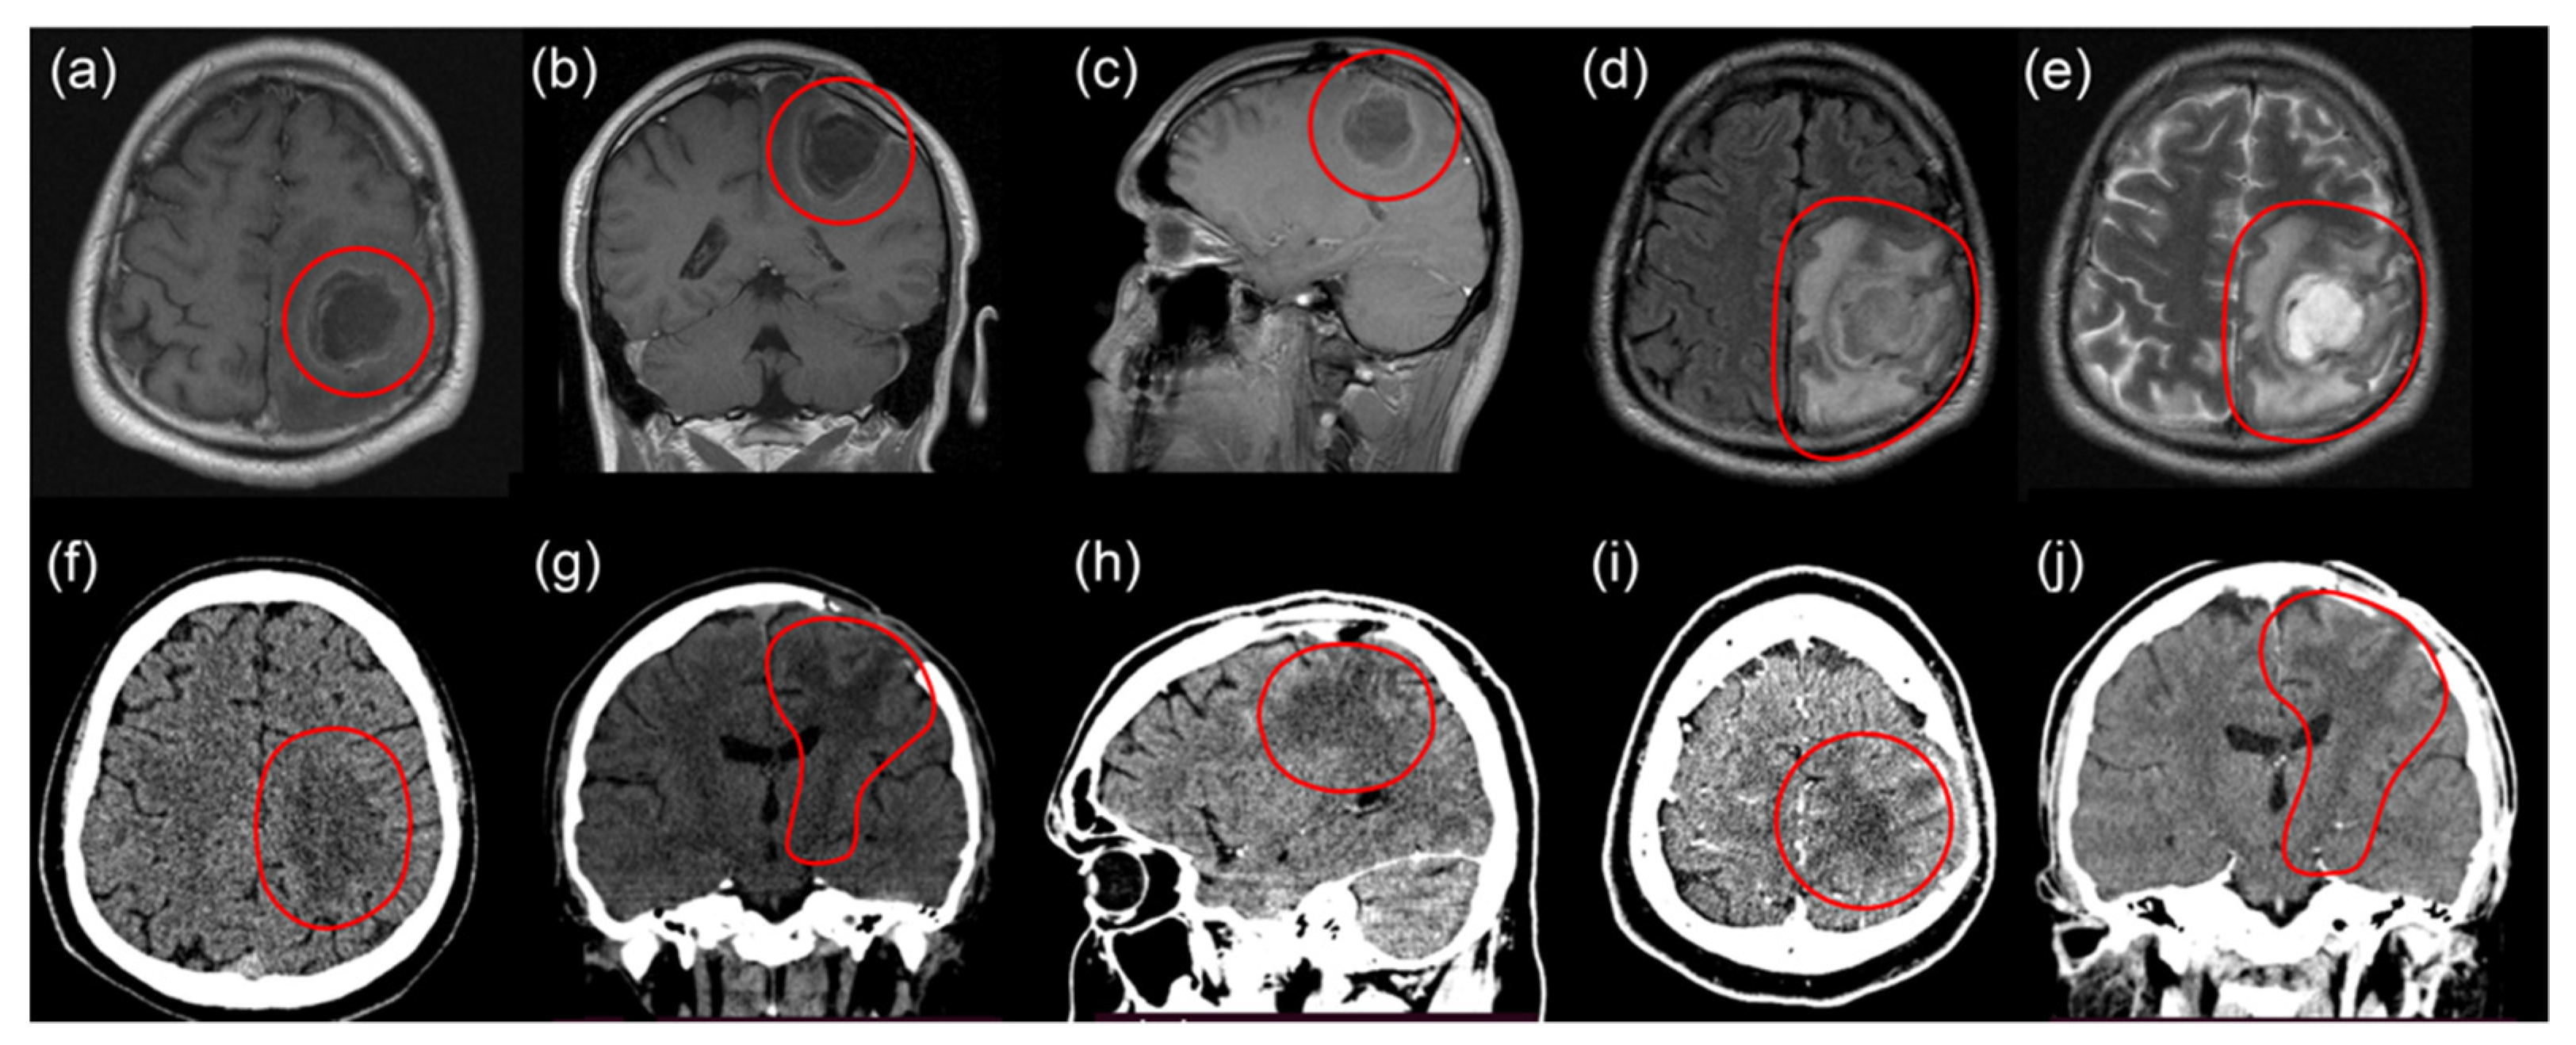

2.2. Second Intervention